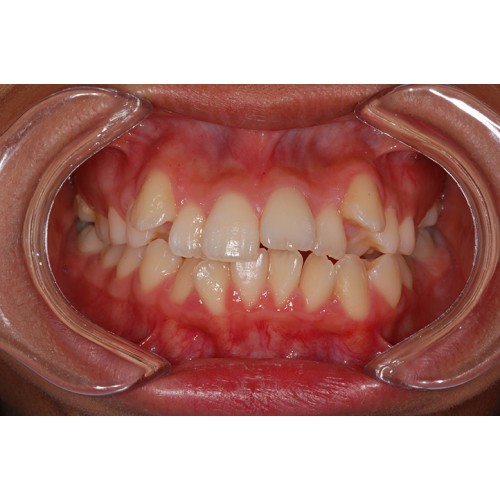

CHUNCHU'S ORTHODONTIC CLINIC# BEFORE_AFTER

춘추치과교정과를 방문해주신 분들의전후 사진을 확인해보세요.